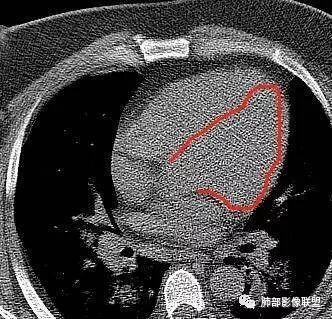

长沟流月去无声:第三点有意见这个人心脏大,左室供血很不好

南边:南边:不大啊冬瓜:熊老师不会考虑病毒感染,爆发性心肌炎吧南边:这个就不敢说淘时光:左心室心腔饱满,室间隔向右室侧有些移位,感觉左室有增大

长沟流月去无声:这个左室心肌都薄了南边:没有做增强啊长沟流月去无声:可以提示大家去看一下流感病毒性肺炎重症,WHO和卫生部都出过指南,建议你们仔细看看指南里危险人群一节,是哪几个